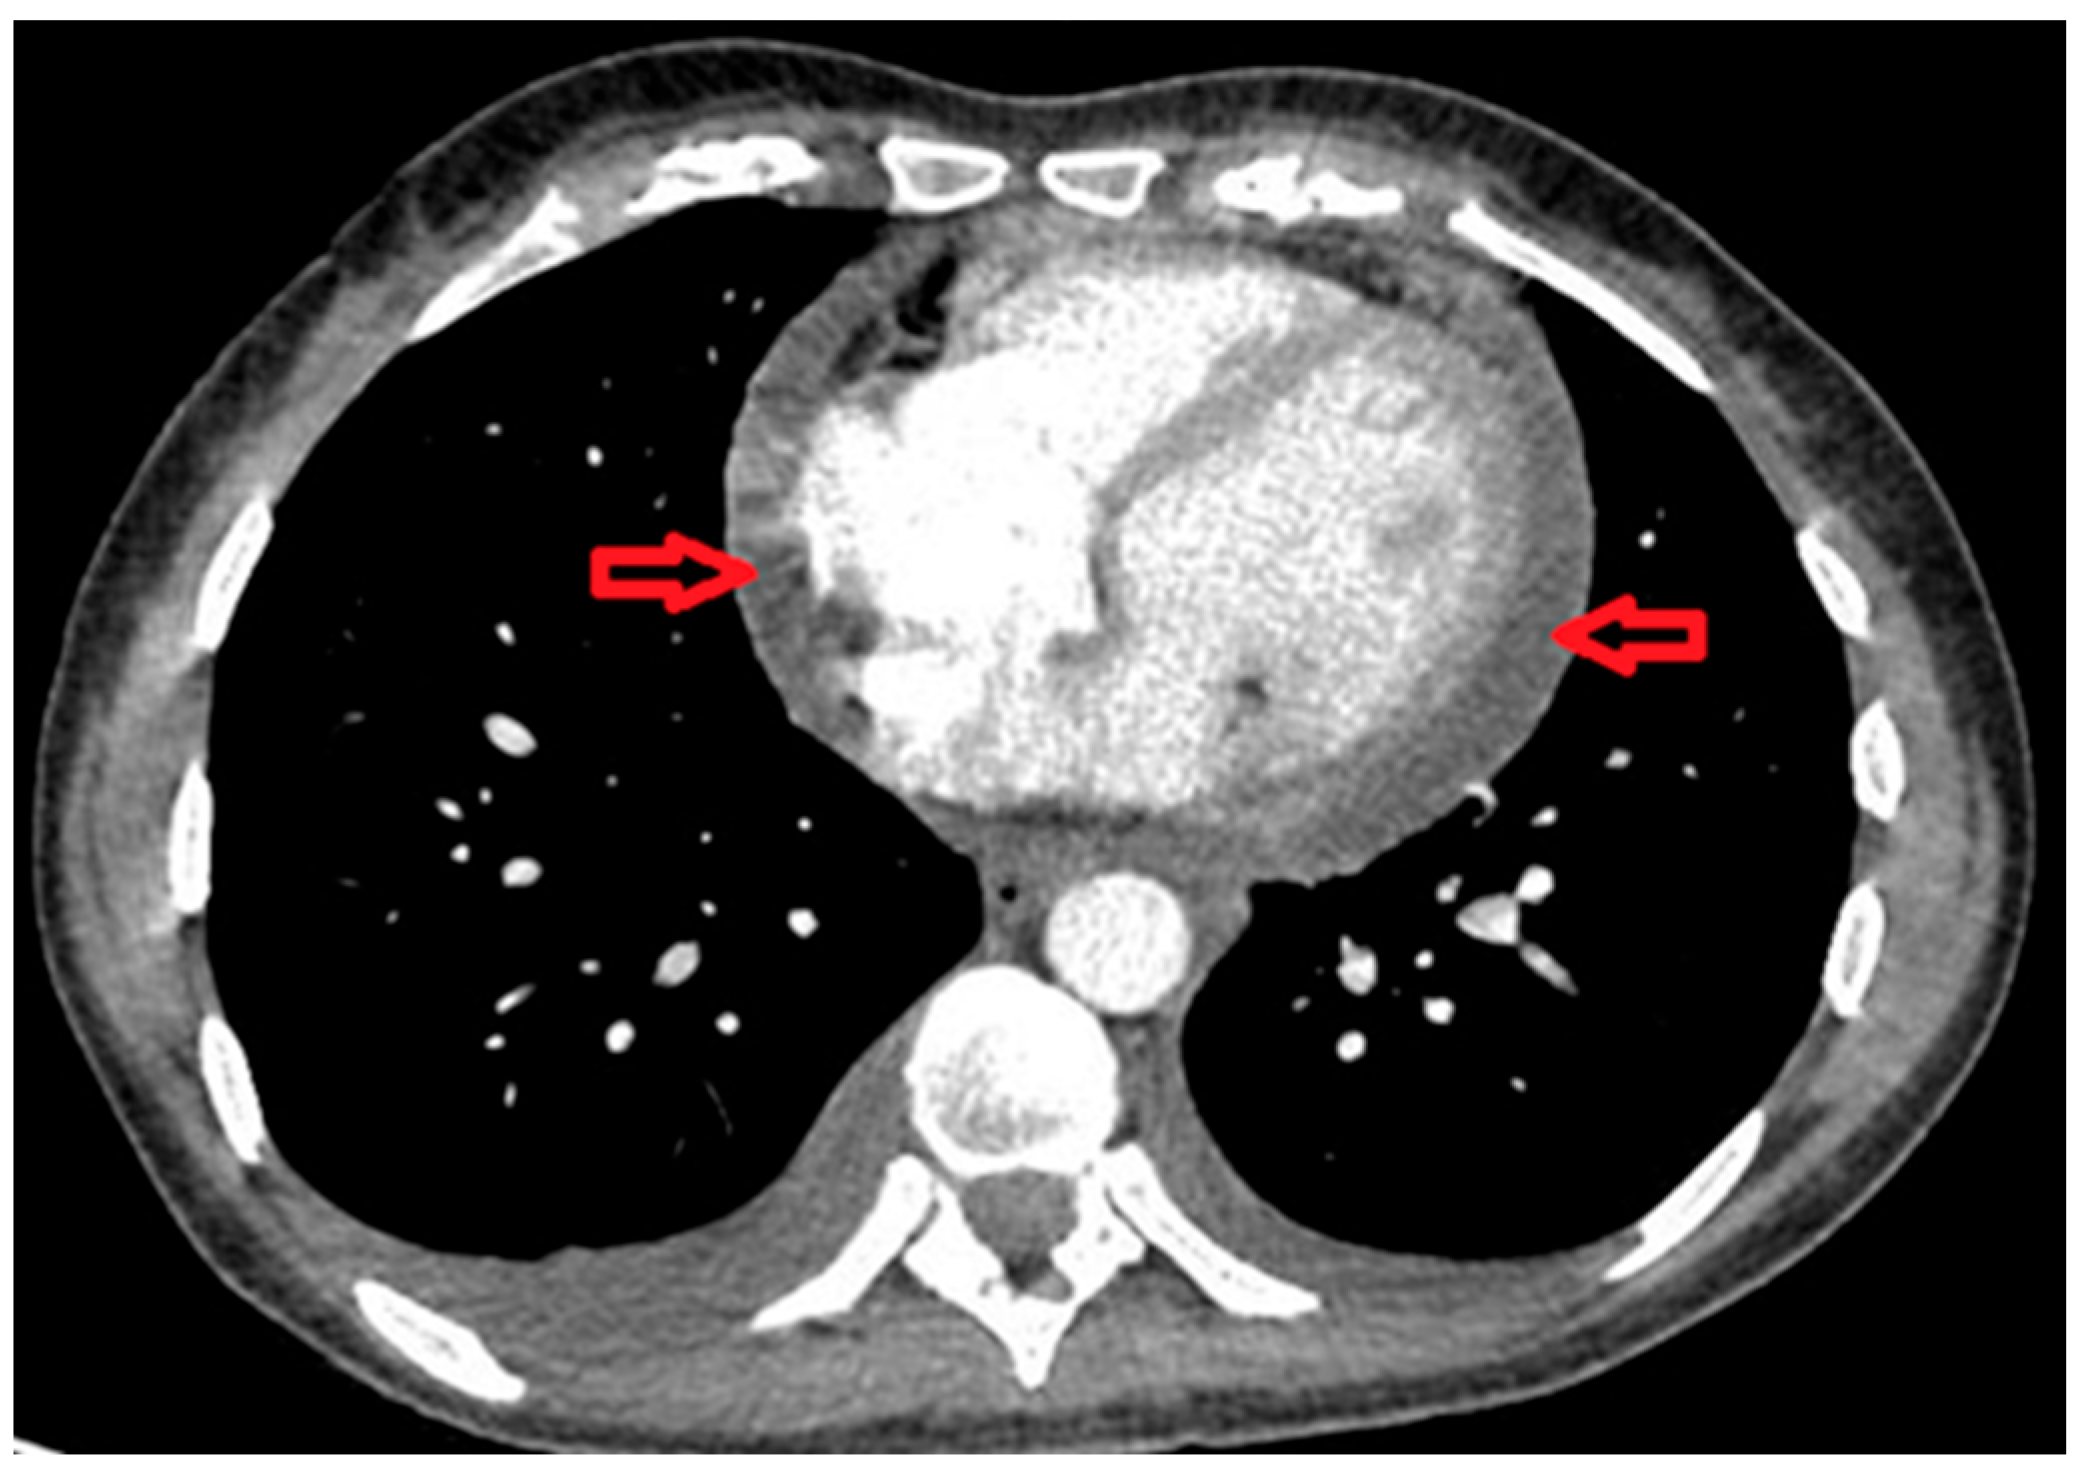

| Echocardiogram Pre-Treatment | Echocardiogram Post-Treatment after 4 Months. |

|---|---|

| A small/moderate global pericardial effusion Normal LV structure and function. Valves appeared structurally and functionally normal Mobile atrial septum, no shunt seen. No evidence of subacute bacterial endocarditis | No obvious residual pericardial effusion Normal LV structure and function No evidence of valve thickening but mild dilation of the non-coronary sinus of Valsalva and trivial AR and MR Normal RV structure and function |